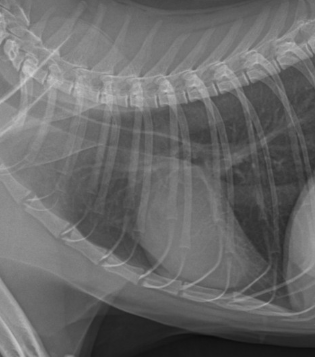

위장관 폐색 환자의 영상 평가 [스페셜 앙코르]

위장관 폐색 환자의 영상 평가[스페셜 앙코르]

위장관 폐색은 임상에서 비교적 흔하게 접하지만,영상 소견의 해석에 따라 진단 속도와 치료 방향이 크게 달라지는 질환입니다.

특히 방사선과 초음파 검사는 폐색 여부 판단과 수술 적응증 결정에 핵심적인 역할을 하지만,정상 위장관 소견에 대한 이해가 부족하거나이물에 의한 폐색 소견을 체계적으로 정리하지 못한 경우임상에서 혼란을 겪기 쉽습니다.

이번 강의에서는정상 위장관 방사선 평가부터 폐색의 전형적인 영상 특징,초음파 스캔의 기본 원칙과 실제 임상에서 바로 활용 가능한 판독 포인트까지단계적으로 정리합니다.

정상 위장관 방사선 평가 방법

위장관 폐색의 방사선학적 특징 정리

위장관 초음파 검사 기본 원칙 및 스캔 노하우

이물에 의한 폐색 소견 정리 및 응급 수술이 필요한 상황 감별 팁

다양한 실제 케이스를 통한 영상 판독 및 임상 적용 정리